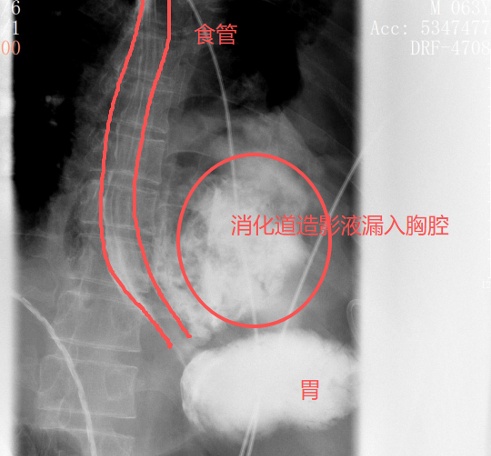

转院时,患者病因成谜。在晨会交班时,胸外科主任刘继先敏锐地捕捉到一个关键细节,他多问了一句:“这个病人,发病前有没有呕吐?”“有!吃完包子之后吐了两次,吐完就开始痛了。”在得到肯定答复后,刘主任立即警觉,判断这可能是一种极为凶险的疾病——“自发性食管破裂”(Boerhaave综合征),并紧急安排了口服钡餐检查。

结果证实了他的判断:

钡剂从食道下段的裂口处

大量漏入了左侧胸腔

刘继先指出,此病救治的关键在于“及时确诊”,发病后的24小时是黄金救治窗口期。一旦超过此时限,食道管壁会严重水肿、糜烂,变得无法缝合修补。

红圈区域是食物残渣、消化液破入食管